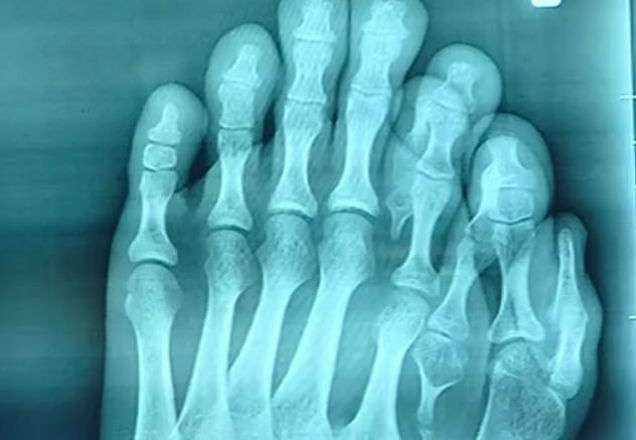

Veja como era o pé do chinês e como ficou:

Médicos conseguiram mudar a vida de um homem que nasceu com nada menos que nove dedos em um dos pés. Identificado como Ajun, o paciente de 21 anos passou por uma cirurgia na cidade de Lufeng, no sul da China, e se recupera no hospital.

Após anos vivendo com a anomalia, Ajun decidiu marcar uma consulta e ver a opinião de um médico. Wu Xiang, doutor responsável pela cirurgia do rapaz, disse que é muito raro ver uma deformidade tão grave não ter sido corrigida por tanto tempo.